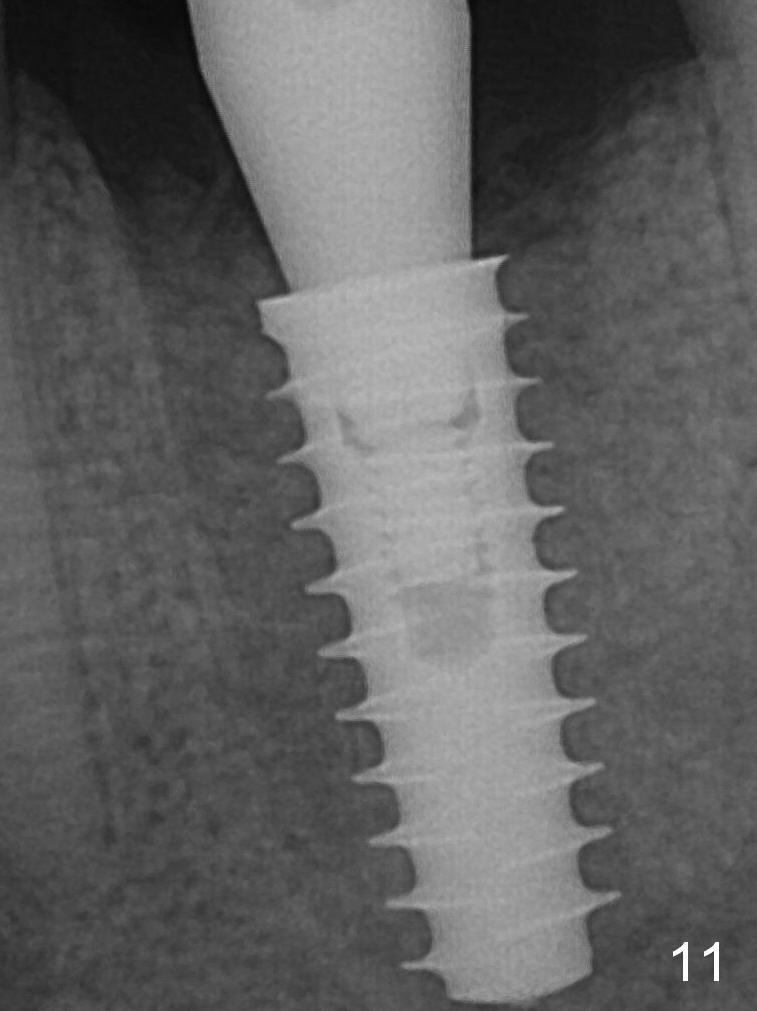

Insertion torque of a 5x13 mm implant is <20 Ncm (Fig.7). A 6.5x4(4) mm pair abutment is placed (A), apparently proper for restoration. Allograft is placed prior to immediate provisional. The patient complains of bad smell from the site 24 days postop. When the provisional is removed, the abutment is found to be mobile. When the latter is removed with local anesthesia, bone graft granules are attached to the socket above the lightly mobile implant. In fact the latter appears to be stable after a few turns by finger. A healing screw is placed; the socket is closed with collagen plug and 4-0 Chromic gut sutures. It appears that a larger implant should have been used to achieve higher torque. Two months later (3 months postop), the coronal end of the implant is partially exposed. A 5x4 mm healing abutment is placed. It appears that the implant is stable. The implant appears to have osteointegrated 4 months postop (Fig.11). Impression is taken. New bone has apparently covered the implant plateau 8 months postop (3 months post cementation (Fig.13 arrows)). The lower two-thirds of socket have disappeared.